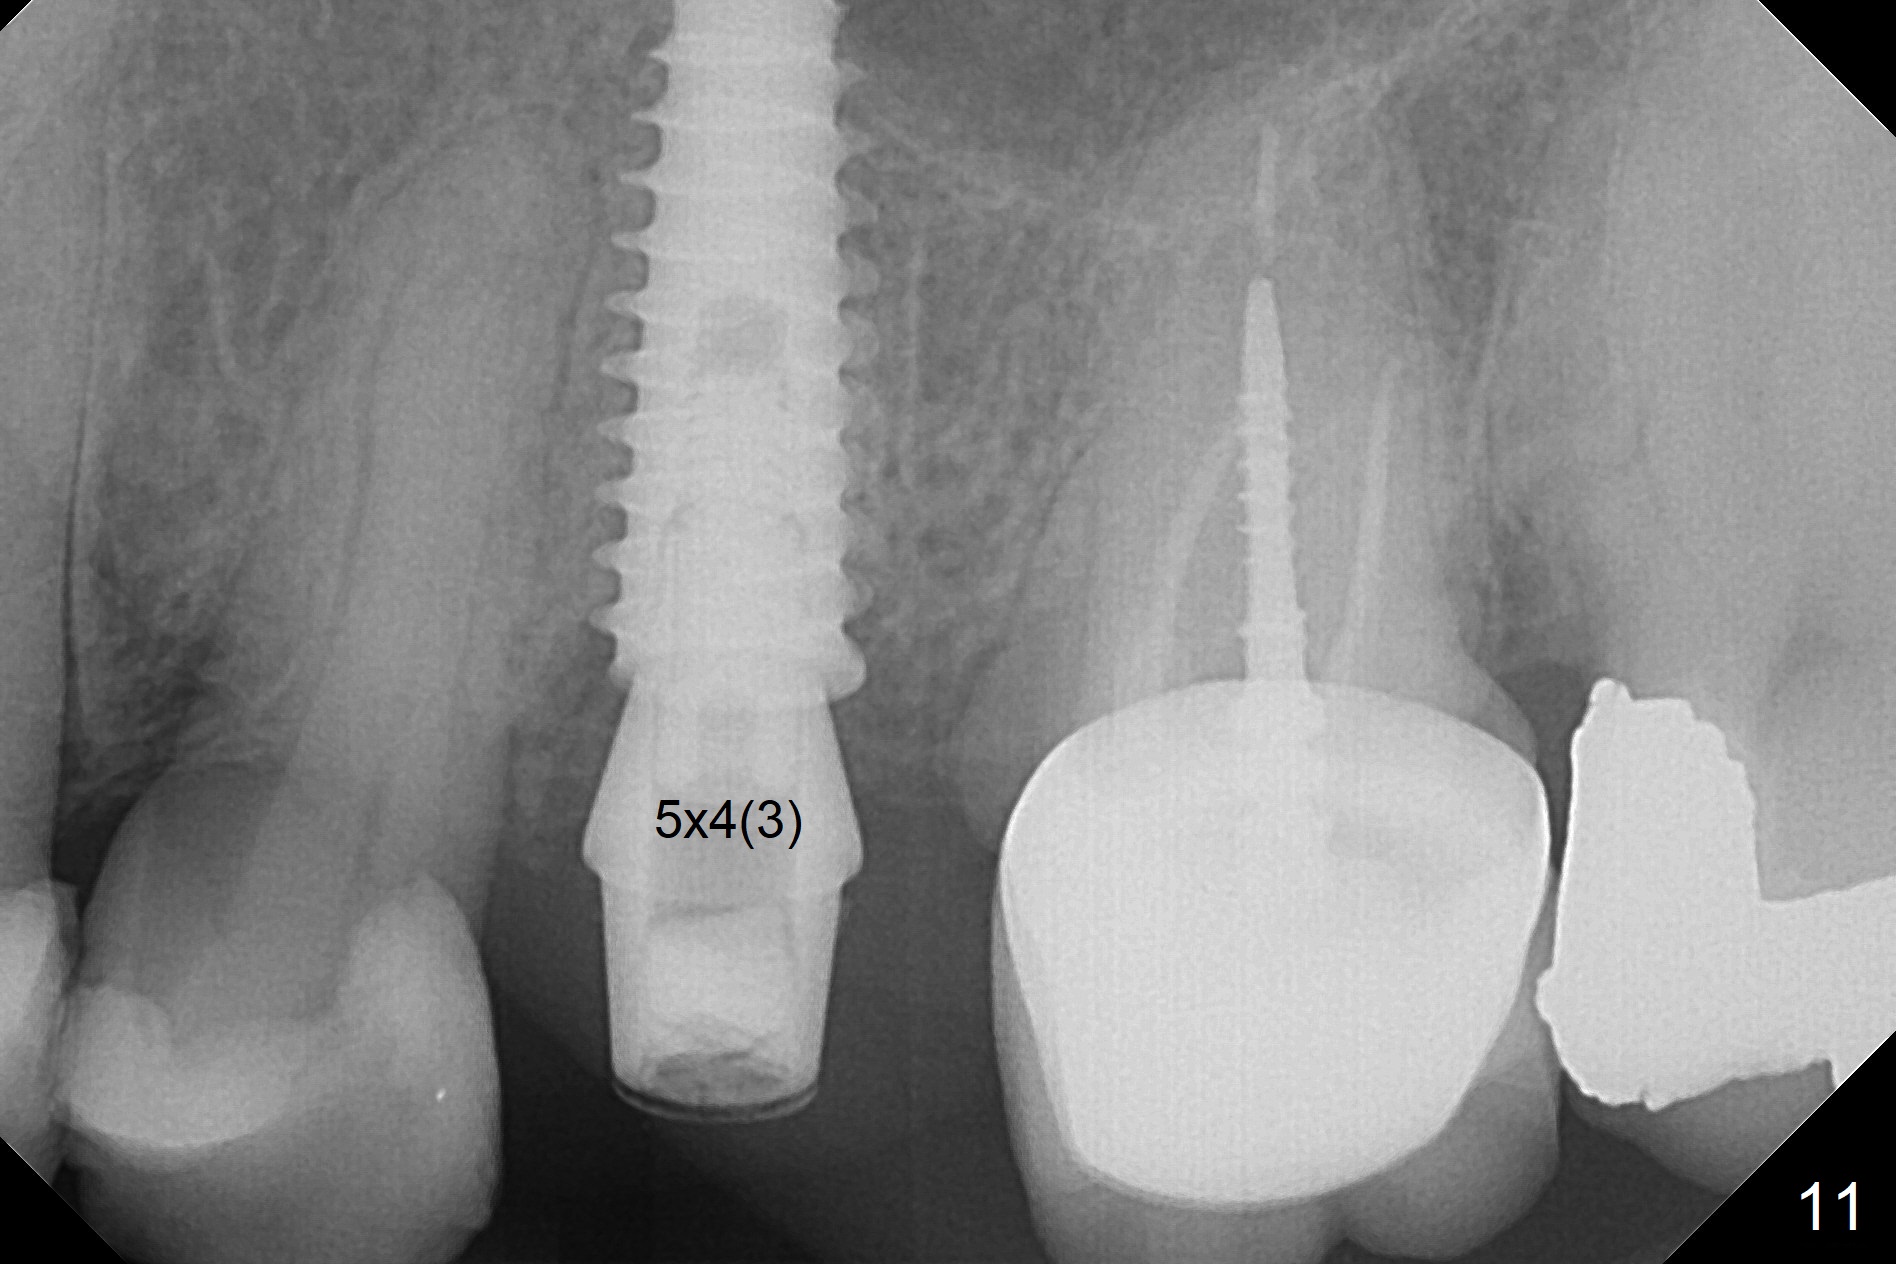

Since the apical native bone is limited at #13 after extraction, no PA is taken until a 4x11 mm dummy implant is placed after 1.6 mm and 3.3 mm drills for 13 mm (Fig.1). After using Lindamann bur to move the osteotomy distal and reusing 3.3 mm drill, the trajectory of a 4.5x11 mm IBS dummy implant improves (Fig.2,3 with low stability). When the implant is removed, the buccal portion of the socket is found to be perforated (Fig.4 P). Although the reason for the perforation is unknown, it is repaired by insertion of a piece of PRF plug, followed by allograft. #1 and 2 in Fig.4 represent the 1st and 2nd osteotomies, as shown in Fig.1 and 2, respectively. The trajectory of the final 5x13 mm implant is acceptable (Fig.5-7, different angulations), so is insertion torque (45 Ncm). After placing a 5.5x4(4) mm abutment, an immediate provisional is fabricated (Fig.8 P) with occlusal clearance (*). The interdental papillae remain in place 12 days postop (Fig.9 *). There is no sign of postop sinus infection. The provisional is loose 18 days postop; the abutment is changed to 5x4(3) mm (Fig.10). It is difficult to catch the mesial margin of the abutment for impression 4 months postop, due to poor oral hygiene and the short cuff (3 mm, Fig.11). The appointment for impression is rescheduled with emphasis on oral hygiene and no wearing the provisional for a few days prior to next appointment. Bone has grown into the space between the 1st and 2nd threads 5 months post cementation (Fig.12) and the bone is normal, solid and dense 2 years 11 months post cementation (Fig.13 >). There is mesial open margin of the tooth #14 (Fig.13,14 *).